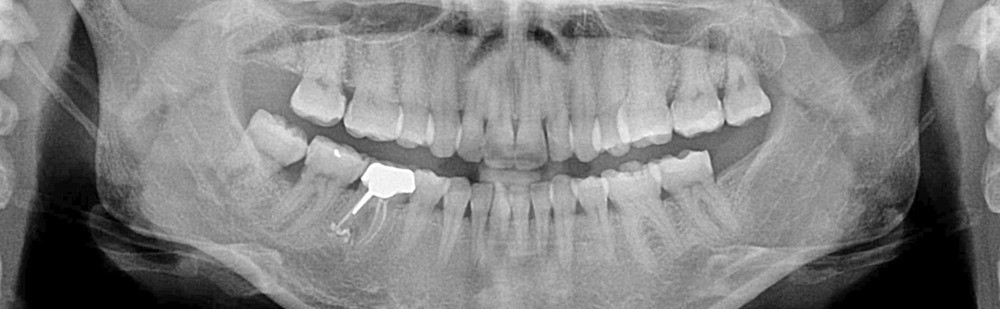

C’est précisément le cas de cette patiente de 33 ans qui présente une classe II squelettique par rétrognathie mandibulaire sur un schéma vertical hyperdivergent associée à une classe II/1 dentaire avec DDA par excès et biproalvéolie. Son profil est convexe, cis-frontal et, sur le plan fonctionnel, on peut observer une dysfonction linguale et une incompétence labiale au repos. Il en résulte une contracture des muscles de la sphère péri-orale lèvres jointes. La formule dentaire n’est pas complète puisque les quatre deuxièmes prémolaires ont été extraites lors d’un premier traitement orthodontique et qu’il y a également agénésie des troisièmes molaires 18 et 38 (fig 1 à 11).

Au regard de ces éléments, la décision thérapeutique choisie intègre une prise en charge orthodontique associée à une chirurgie orthognathique d’avancement mandibulaire et à une mentoplastie. L’étape initiale du traitement orthodontique consiste en la levée des compensations dentaires qui se traduit par la correction de la proalvéolie mandi– bulaire dans le but de pouvoir corriger la classe II squelettique et dentaire par avancement chirur- gical de la mandibule. Pour cela, des mini-vis d’ancrage sont positionnées distalement aux secteurs 3 et 4, enfouies à la base des branches mandibulaires avec des chaînettes métalliques émergentes dans la cavité buccale. L’objectif est d’assurer le repositionnement incisif mandibulaire grâce à des modules élastiques.